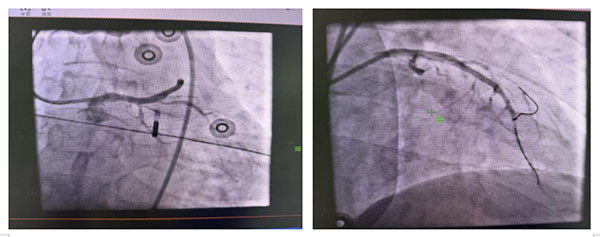

在机械辅助支持下,行急诊冠脉造影,确认三支闭塞,前降支近段急性闭塞,右冠近段慢性闭塞,回旋支远端慢性闭塞,优先开通前降支罪犯血管,导丝通过前降支,球囊扩张,快速植入1枚支架,血管开通后,血流恢复TIMI3级,恢复心肌血供,对其余慢性闭塞病变分次处理,避免长时间缺血再灌注损伤,血压维持在98/60mmHg,心率108次/分。

支架术后: